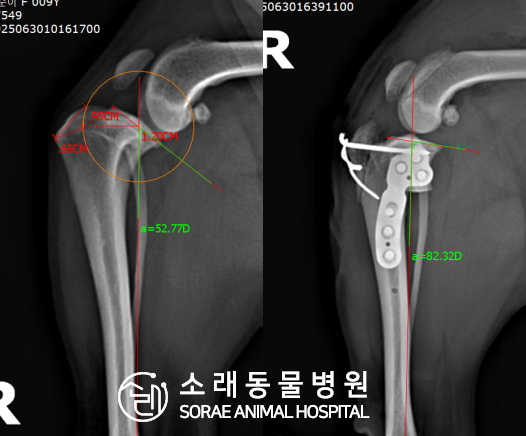

계산식으로 사전에 계획해두었던 플랜에 따라 경골을 절제하고

플레이트와 스크류를 사용하여 임플란트를 적용해 주었습니다.

반대 방향으로 밀려나 어긋나있던 대퇴골과 정강이가

제 자리를 찾으면서 무릎의 각도가 교정된 것을 확인할 수 있습니다